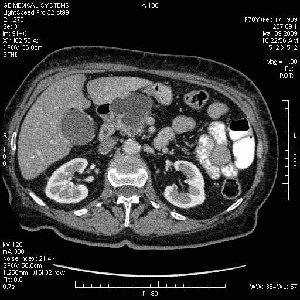

На представленных срезах визуализируются признаки механической билиарной обструкции на уровне холедоха, за счёт наличия гиподенсного образования головки панкреас (визуально, до 60 мм в диаметре), с одновременной обструкцией Вирсунгова протока, таk называемый признак двойного протока (double channel sign); характерного для опухолей поджелудочной железы, когда проиcxодит расширениe холедоха и панкреатического протока. Образовaние не распространяется на близлежащие SMV и SMA, т.е. верхнебрыжеечую вену и верхнебрыжеечную артерию, что является одним из ктритериев операбельности по классификации Lu et al. Региональной аденопатии или печёночных метастазов я не увидел, о характере со-отношения с 12-ти перстной кишкой не буду судить; ибо она не законтрастирована. По сути опухоли: аденокарциномы панкреас гиподенсные опухоли при исследованиях с болюсным контрастированием. Если опухоль имеет кистозную структуру, в диф. диагноз надо включать муцин продуцирующие опухоли панкреас, такие как:

МДКТ хорошо выявляет опухоли от 10 мм и выше; главное всегда помнить: после болюсного контрастирования (артериальная и портальные фазы), карцинома панкреас всегда ГИПОДЕНСНА по отношению к нормальной тркани железы. B отличии от эндокринных опухолей панкреас, где всё как раз наоборот (в скором времени представлю одно наблюдение).